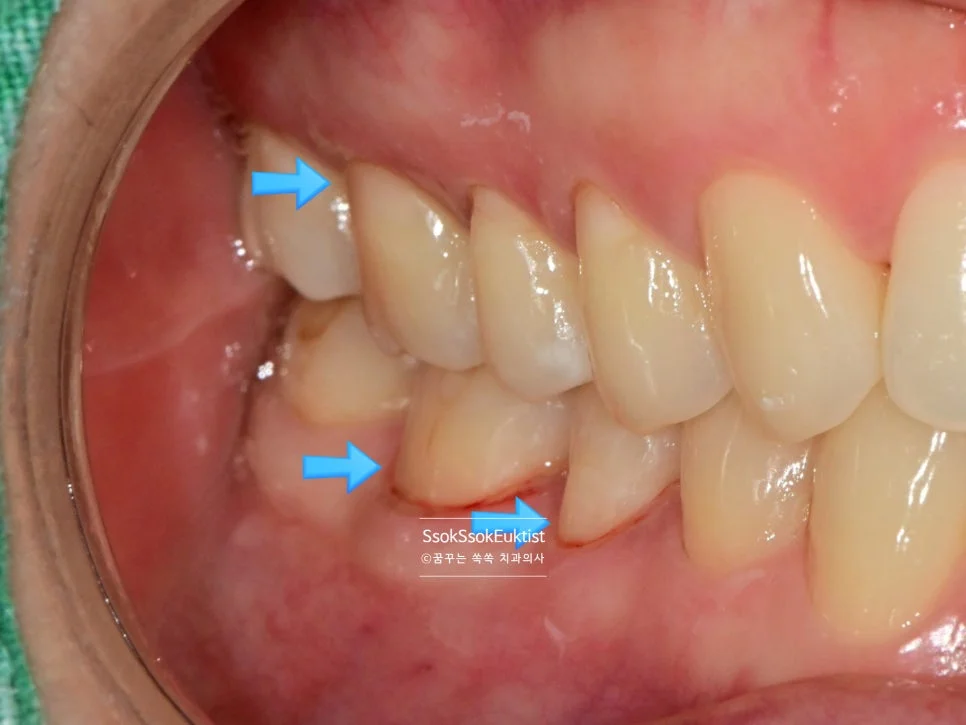

GI 치료 전 — 대부분 V자, 일부 U자 형태

형태를 보면 대부분 V자인데 하나 정도만 U자 형태를 보이고 있습니다. 이런 경우 강한 칫솔질이 치경부 마모증을 악화시켰다고 볼 수 있습니다!

이 사례에서는 GI(Glass Ionomer, 글라스 아이오노머)로 충전을 시행하였는데요.